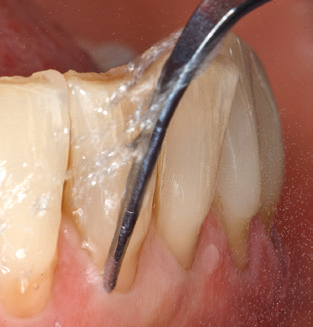

Abb. 4: Für das Sondieren an dentalen Implantaten sind biegsame, millimeterskalierte Sonden empfehlenswert (z.B. Colorvue Kit PCV11KIT6, Hu-Friedy). – Abb. 5a und b: Eine gerade Arbeitsspitze (1P, W&H Dentalwerk Bürmoos GmbH) ist universell für die Instrumentierung natürlicher Zähne geeignet. – Abb. 6: Für die Bearbeitung schwer zugänglicher Bereiche der Zahn- und Wurzeloberflächen (z.B. Furkationen) bieten sich gebogene Arbeitsspitzen (3Pr/3Pl, W&H Dentalwerk Bürmoos GmbH) an. – Abb. 7: Die spitz zulaufende sechseckige Implantatreinigungsspitze (1I, W&H Dentalwerk Bürmoos GmbH) ermöglicht eine atraumatische und effiziente Reinigung der Kronen- und Abutmentoberflächen. – Abb. 8: Für die manuelle Instrumentierung der Implantatoberflächen sind Titan- oder Carbonküretten geeignet.

Die gute Ausleuchtung des Arbeitsfeldes stellt eine wesentliche Erleichterung dar. Bei dem von den Autoren genutzten System ist dies gelungen, indem ein 5­facher LED­Ring in das Handstück integriert wurde. Natürlich werden für dieses System unterschiedliche Arbeitsspitzen für die jeweiligen Indikationsbereiche angeboten. Eine gerade, universell einsetzbare Spitze ist das Basisinstrument zur maschinellen Instrumentierung natürlicher Zähne (Abb. 5a und b). Für schwer zugängliche Bereiche im Seitenzahnbereich werden gebogene Spitzen angeboten, die auch einen Zugang zu freiliegenden Furkationen ermöglichen (Abb. 6).